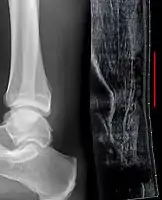

Radiography can also be used to indirectly identify Achilles tears. Radiography uses X-rays to analyse the point of injury. This is not very effective at identifying injuries to soft tissue. X-rays are created when high energy electrons hit a metal source. X-ray images are acquired by utilising the different attenuation characteristics of dense (e.g. calcium in bone) and less dense (e.g. muscle) tissues when these rays pass through tissue and are captured on film. X-rays are generally exposed to optimise visualisation of dense objects such as bone while soft tissue remains relatively undifferentiated in the background. Radiography has little role in assessment of Achilles' tendon injury and is more useful for ruling out other injuries such as calcaneal fractures.[13]

Achilles tendon avulsion seen on plain X-ray

Achilles tendon rupture

Transverse plane/Achilles tendon rupture

Achilles tendon rupture seen on ultrasound. Note discontinuity over several centimeters (red line). No fracture or avulsion (radiograph).